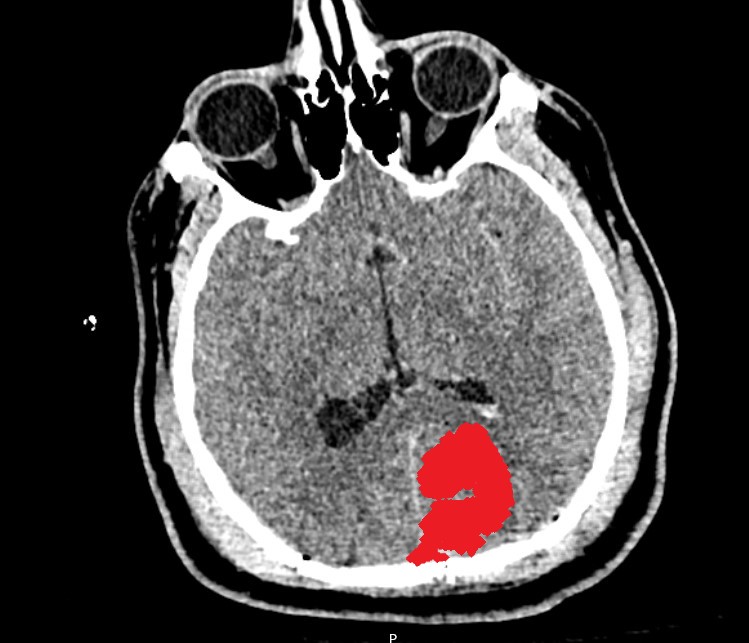

Intraparenchymal Hemorrhage

This is an Intraparenchymal Hemorrhage (IPH). This bleeding occurs inside of your brain. An IPH is a severe injury because there are no layers that separate your brain from that blood that collects within it. On CT, this bleeding will look like a collection of blood. This blood can cause your brain to 'shift' and damage your brain from the inside out. It commonly occurs in more than one area of the brain after a traumatic injury.